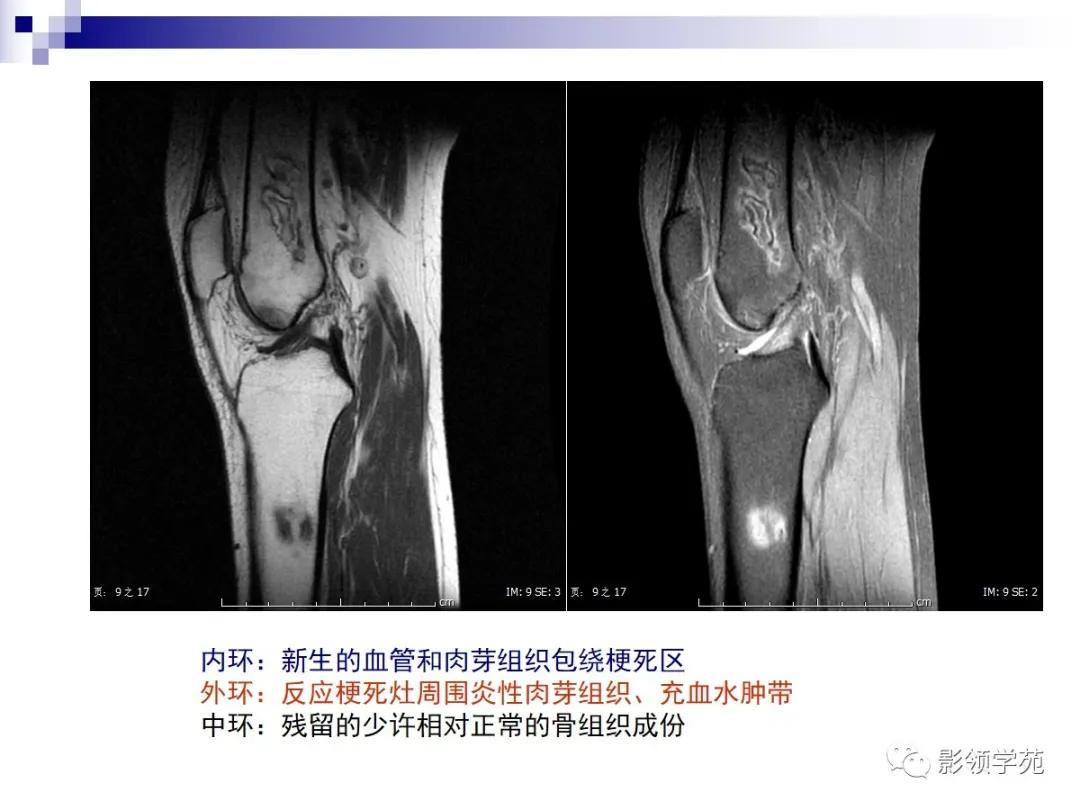

MRI:呈不规则“地图状”异常信号,典型征象是病灶边缘呈“三环征”,由外向内

T1WI呈 低-高-低

压脂T2WI 高-低-高